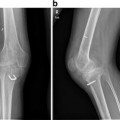

Technical errors in ACL reconstruction include malpositioned tunnels, inadequate notchplasty, improper tensioning, and insufficient graft fixation. More than 70 % of technical errors are due to malpositioned tunnels [16, 24], with anterior femoral tunnel positioning the most common error. Positioning of the femoral tunnel is extremely important to knee function, as the origin of the ACL is close to the axis of rotation of the knee [8]. Small changes in the femoral attachment of the ACL have significant effects on the knee’s biomechanics. Poor tunnel placement leads to excessive changes in graft length over the knee’s range of motion, leading to plastic deformation and consequently loosening of the graft. An anterior femoral tunnel places increased stress on the graft in flexion, resulting in decreased flexion, pain with flexion, and stretching of the graft [15]. Similarly, a femoral tunnel too posterior increases the stress on the graft in extension, resulting in loss of extension, pain on extension, and stretching of the graft as well. Over time, both scenarios could result in deformation of the graft to the point of incompetency.

The femoral tunnel can also be incorrectly positioned in the coronal plane. A tunnel too close to the central axis of the femur, at the so-called 12 o’clock position, will result in adequate anterior restraint but poor rotational stability [25, 26]. Failure to control for rotation will result in continued instability episodes with cutting or pivoting activities. The femoral tunnel needs to be positioned more horizontally on the medial wall of the lateral femoral condyle to best control for anterior and rotation stability [27].

The effects of tibial tunnel positioning are more forgiving on graft tension than femoral tunnel positioning, but also play a role with potential impingement of the graft. Similar to femoral tunnel positioning, an anterior tibial tunnel will result in increased graft tension in flexion, whereas a posterior tibial tunnel will result in decreased tension in extension. In addition, an anterior tibial tunnel will cause impingement of the graft against the notch in extension, resulting in pain and/or decreased extension [28]. A posterior tibial tunnel will impinge against the PCL in flexion, causing pain and/or decreased flexion. Medial or lateral placement of the tibial tunnel may also cause impingement against the medial and lateral walls of the intercondylar notch [29]. The tibial tunnel position is not the only factor in graft impingement. Typically, the ACL graft is larger than the native ACL, so adequate space may not be available within the intercondylar notch. Even with ideal tibial tunnel position, a notchplasty may be required in some knees to open up the space available for the incoming graft to prevent impingement from occurring [30, 31]. Prevention of impingement is important, as repetitive friction from knee range of motion may cause persistent pain and swelling, as well as ultimately lead to graft failure and knee instability.